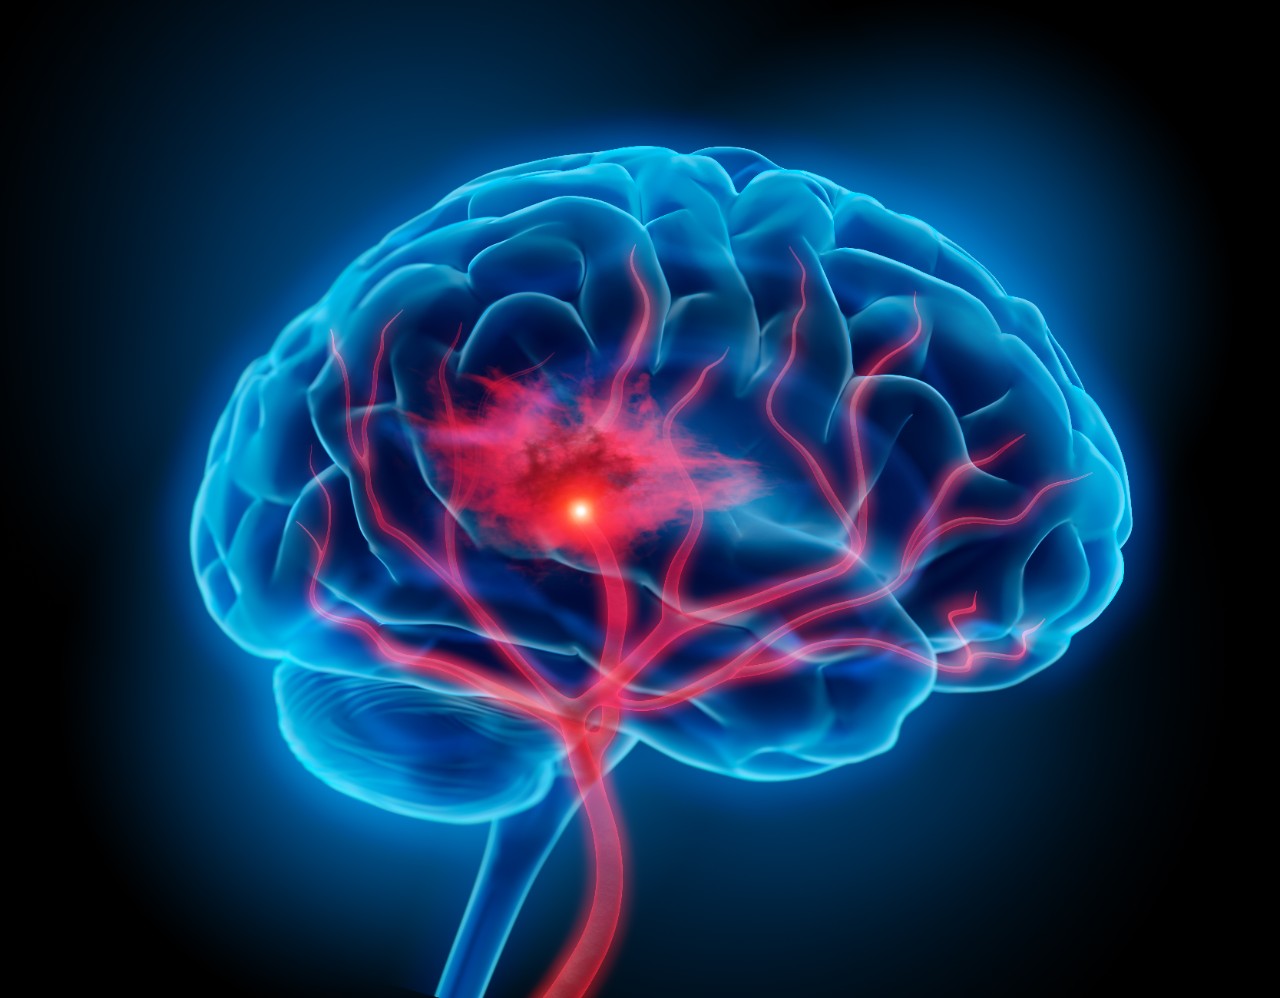

Ischemic strokes, the most common form of strokes, are caused by a lack of blood flow and oxygen to specific parts of the brain. When a stroke patient arrives at the hospital, Aziz explained, they undergo a CT scan that can help doctors assess the severity of the damage the stroke has caused using a 10-point scale.

Featured photo at top of illustration of brain with stroke symptoms. Photo/PeterSchreiber.media/iStock.